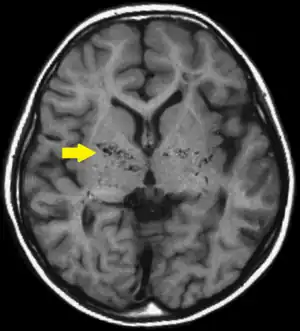

![]() | |

| T1-weighted MR image of moyamoya disease. Flow void in the basal ganglia is indicated by the arrow. | |